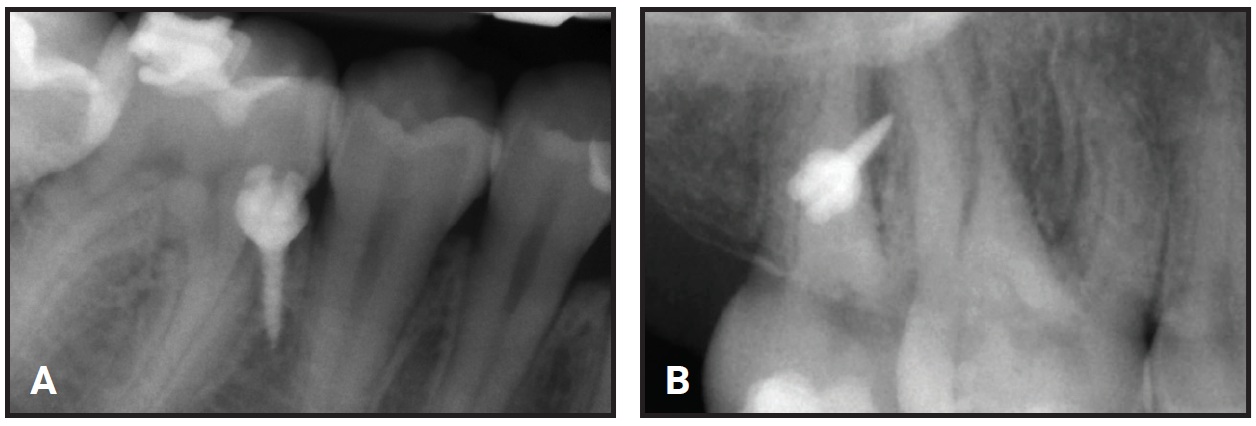

The aims of the second phase were to refine the occlusion and the alignment, fully center the midlines, and resolve the right posterior scissor bite. To improve the predictability and efficiency of the scissor-bite correction, a hybrid approach was planned using aligners with fixed buccal sectional appliances, orthodontic miniscrews, and criss-cross elastics. Brackets*** were bonded to the upper right first and second molars and the lower right first and second molars, and .016" × .022" nickel titanium wires† were placed (Fig. 5).

Fig. 5 A. Miniscrew‡ inserted in interradicular space between right second premolar and first molar. B. Miniscrew inserted in interradicular space between upper right first and second molars.

A 1.5mm × 8mm orthodontic miniscrew‡ was manually inserted into the buccal interradicular space between the lower right second premolar and first molar. An .017" × .025" stainless steel sectional wire† was attached from the screw head to the buccal surface of the lower right first molar to obtain indirect anchorage for buccal uprighting of the lower right second molar. Temporary bite turbos were built with light-cured flowable resin on the occlusal surfaces of the mandibular first molars to facilitate scissor-bite correction.

After the sectional appliances were placed, new intraoral scans were taken and a refinement setup was performed, involving eight trays in each arch. Before the refinement aligners were delivered, a 1.5mm × 8mm palatal miniscrew was inserted in the interradicular space between the upper right first and second molars, and metal buttons were bonded to the palatal surfaces of the upper right second molar and the lower right second molar. An elastic chain was connected directly between the miniscrew and the palatal button on the upper right second molar to exert an intrusive force for the scissor-bite correction (Fig. 6).

Fig. 6 A. Intrusion of upper right second molar with elastic chain between lingual button and miniscrew. B. Criss-cross elastic placed between buccal tube hook on upper right second molar and lingual button on lower right second molar.

A criss-cross elastic was applied between the hook on the buccal tube of the upper right second molar and the lingual button on the lower right second molar.